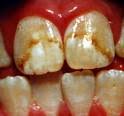

Esmalte moteado

Anomalia de la cavidad bucal, el cual indica la falta de esmalte en los dientes, lo cual no cubre la totalidad del mismo presentando zonas expuestas, la causa principal es el fluoruro.